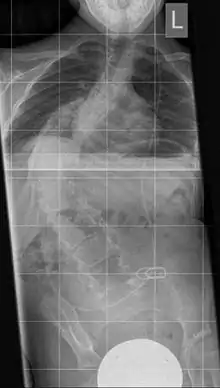

Vertical Expandable Prosthetic Titanium Ribs (VEPTR) is a product of Synthes for the treatment of childhood deformities of the thorax.[1][2][3][4] It is a special form of a lengthenable rod ("Growing Rod"). An alternative system is the USS pediatric for older children, also from Synthes.

The instrument is used to dilate a too small or too narrow rib thorax in severe thoracic deformity. It consists of a telescopic "titanium rib" in curved form with several holes in a row for fixing in the desired length. A prolongation can be carried out after 6 months. The fixation takes place between two ribs or between a rib and the iliac crest. This results in an indirect erection of the deformed spine, resulting in an increase in the volume of the thoracic cavity along with the lung.